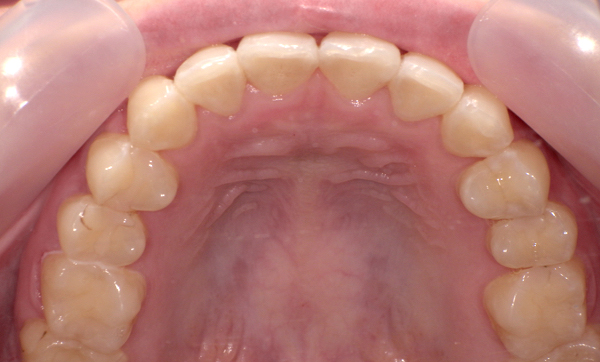

症例_001 前歯「八の字/V字型」症例

治療期間:17ヶ月金額:54万円+税20代女性八の字/V字型

| Before | After |